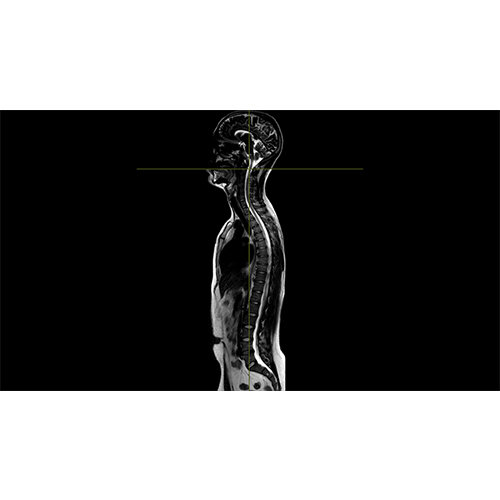

Segmentation of tissue (e.g., isolating the brain, differentiating gray and white matter) is performed using region-growing methods, filter operations as well as the application of 3D templates. Using the mouse it is very easy to explore a 3D volume with superimposed pseudocolor-coded statistical maps in a four-window representation showing a sagittal, coronal, transversal and oblique section. Based on a (segmented) 3D data set a three-dimensional reconstruction of the subjects' head and brain can be calculated and displayed from any specified viewpoint using volume or surface rendering.

Volume Rendering

Volume rendering is performed with a very fast ray casting algorithm; lightning calculations are based on Phong-shading. Surface rendering of reconstructed surfaces is performed using OpenGL. Using texture mapping, a reconstructed surface (e.g., head or brain) may be sliced in real time, showing both surface and volume data at the same time. Initial polygon meshes serve as the basis for surface finding, cortex inflation and cortex flattening computations.